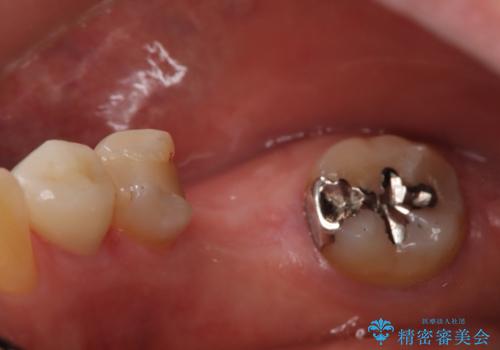

- 定期的に本院に通院されている患者様で、前歯の揺れがあると相談されました。下の奥歯が左右合わせて3本喪失されており、噛み合わせの負担が前歯にも集中していることを説明しました。右下6番の歯に関しては、事前の診査で十分な骨量がありましたのでインプラントを1本埋入しました。左下5番・6番にも本来はインプラントを埋入したかったのですが、骨量が十分でなく、骨を増やす処置をすると神経が近くリスクがあることから、審美性に配慮した金属のばねが見えないノンクラスプデンチャーを製作しました。また、このとき入れ歯を支える左下7番に根尖病変がありましたので、根管治療も行っております。(根管治療は当院院長で専門医を持つDr.林が担当しています。)治療終了後、約1年が経過しましたが、問題なく経過しており患者様も喜ばれていました。